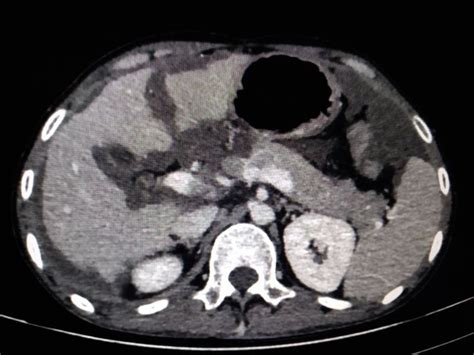

So, what exactly is Pseudomyxoma Peritonei ? For starters, it’s a rare disease that primarily affects the peritoneum, which is the lining of the abdominal cavity. Essentially, it’s characterized by the gradual accumulation of a gelatinous substance, known as mucin, within the abdomen. This mucin is produced by mucinous tumors, most commonly originating from the appendix, but sometimes from the ovaries or other abdominal organs. Over time, this mucin builds up, causing the abdomen to distend and leading to a host of uncomfortable and sometimes severe symptoms. Think of it like a slow-growing, jelly-like invasion that puts pressure on your organs. It’s important to note that PMP is not a single disease but rather a spectrum of conditions, often classified by the grade of the tumor cells and the amount of mucin present. This is why understanding the specifics of each case, and thus the latest pseiidmse sesdtirolse news , is so critical for personalized treatment.

The rarity of PMP means that many healthcare professionals may have limited experience with it. Diagnosis can often be challenging and delayed, with symptoms sometimes being mistaken for other, more common abdominal issues like appendicitis, ovarian cysts, or irritable bowel syndrome. This diagnostic delay can be incredibly stressful for patients. The insidious nature of PMP means that by the time it’s correctly identified, the disease may have spread significantly within the abdominal cavity. The accumulation of mucin can displace organs, impede digestion, and cause pain and discomfort. Furthermore, the mucinous material itself can become thick and viscous, leading to bowel obstruction, hernias, and other serious complications. The psychological toll on patients and their families during this diagnostic odyssey cannot be overstated. It’s a journey filled with uncertainty, fear, and the constant search for answers and effective treatments. This is precisely why staying connected to reliable sources of Pseudomyxoma Peritonei news is a lifeline for many, offering not just information but also a sense of community and shared experience.